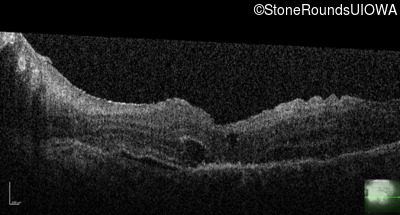

Optical Coherence Tomography - Right - 20/50 -3

Exemplar / OCT Stack